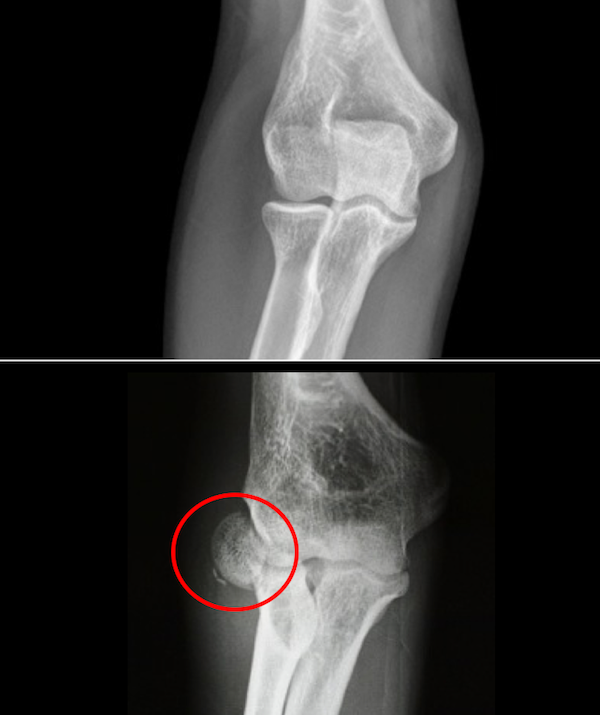

From www.researchgate.net

Radiograph in AP and lateral views showing the radial head fracture Collar And Cuff Radial Head Fracture Learn about the causes, symptoms, and treatment of radial head fractures, which are common elbow injuries. Learn about the anatomy, classification, presentation, diagnosis, and treatment of radial head fractures, a common elbow injury. It’s important that you reduce the use of this as your pain improves to. Find out how long it takes to heal and. A collar and cuff. Collar And Cuff Radial Head Fracture.